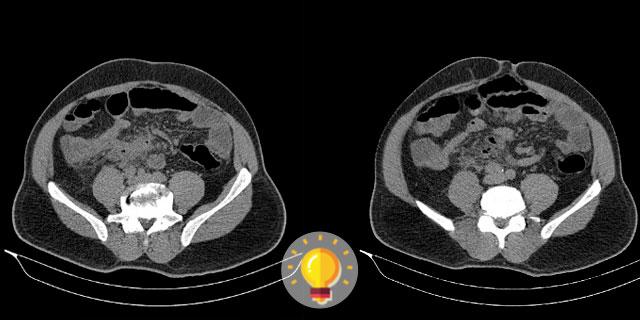

Paciente sexo masculino, 61 anos, com quadro de dor abdominal em mesogástrio, sem irradiação, sem febre. Qual é o diagnóstico?